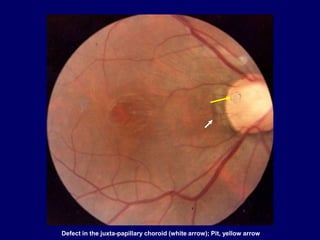

Defect in the juxta-papillary choroid (white arrow); Pit, yellow arrow

Defect in the juxta-papillary choroid ,(white arrow ); Pit, (yellow arrow)

Pit, and lamellar macular hole

Defect in thejuxta-papillary choroid (white arrow); Pit, yellow arrow

Defect in thejuxta-papillary choroid ,(white arrow ); Pit, (yellow arrow)

Pit, and lamellarmacular hole